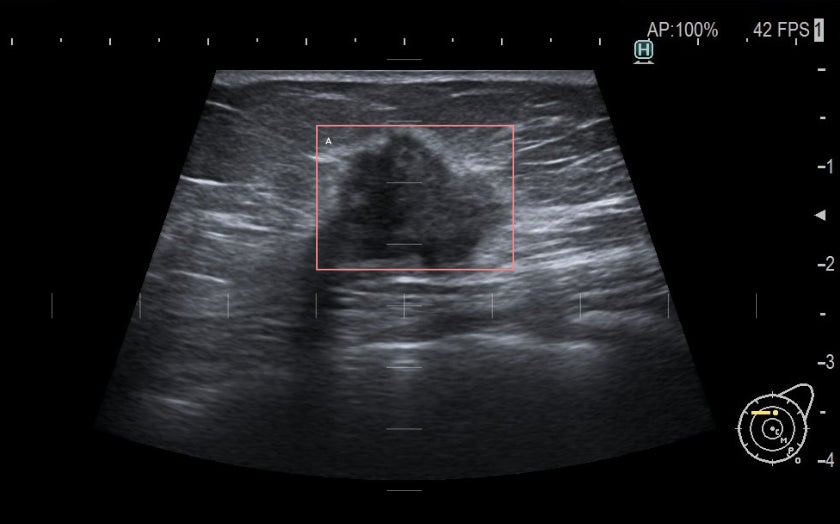

乳癌超音波画像AI診断支援ソフトウェア「スマートオピニオン METIS Eye」の医療機器承認取得

株式会社Smart Opinion(本社:東京都港区、代表取締役社長:山並 憲司)は、乳癌超音波画像AI診断支援ソフトウェア「スマートオピニオン METIS Eye」の製造販売承認(薬事承認)を取得したことをお知らせいたします。深層学習を活用した乳がんエコー検査で撮像するエコー画像を対象にした医療機器プログラムとなります。今後は、2024年夏の販売開始を目指し、準備を進めてまいります。

乳がんの精密検査の要否が疑われる所見を検出する感度が94.4%の医療機器プログラム

本プログラムは、慶應義塾大学病院との共同研究を通じて開発した技術をベースに、医師の読影を補助し、見落とし防止を支援することを目的に開発しました。

乳がん検診は精密検査を行うべき症例か否かを判断する場であることから、本プログラムは、精密検査の必要性が疑われる病変候補部位と、当該病変候補部位を国際的な基準であるBI-RADSカテゴリー分類に基づき判定し、精密検査の必要性の有無を検出します。

精密検査の必要性が疑われる所見の検出感度は94.4%であり、また、医師単独で読影した場合の正診率69.3%と比べて、本プログラムを用いて読影した場合は感度73.1%となり、有意な読影精度の向上が認められました。[1]